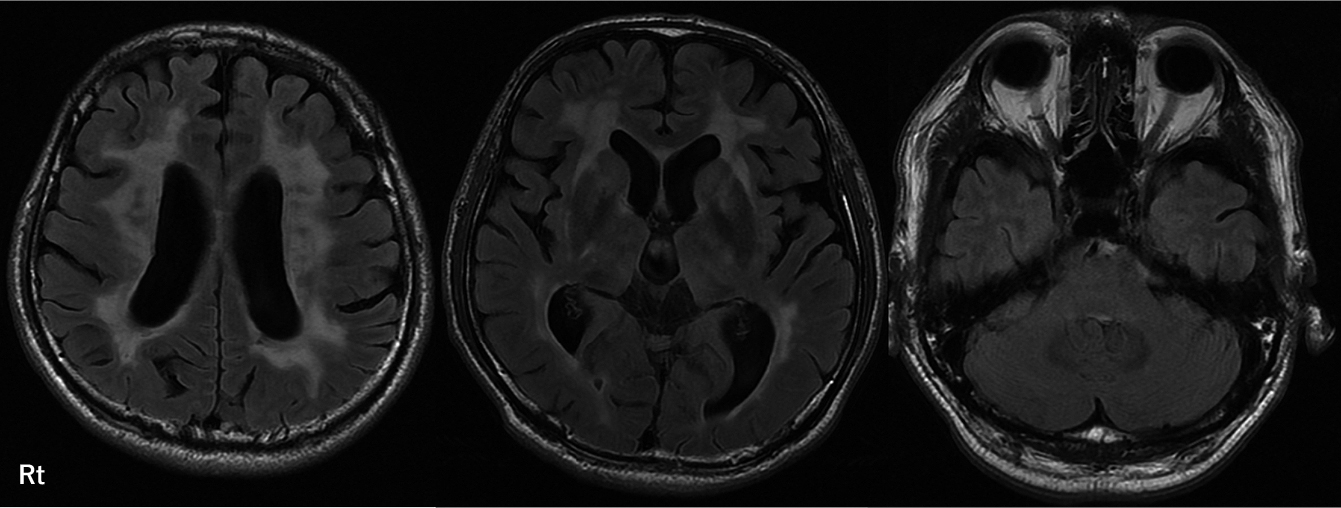

Claustrum signを呈したfebrile infection related epilepsy syndrome(FIRES)の55歳女性例

Febrile infection-related epilepsy syndrome (FIRES) with the claustrum sign in a 55-year-old woman: a case report

赤尾 剛, 市川 大, 藤盛 寿一, 中島 一郎

Go Akao, Dai Ichikawa, Juichi Fujimori, Ichiro Nakashima

2026/03/11